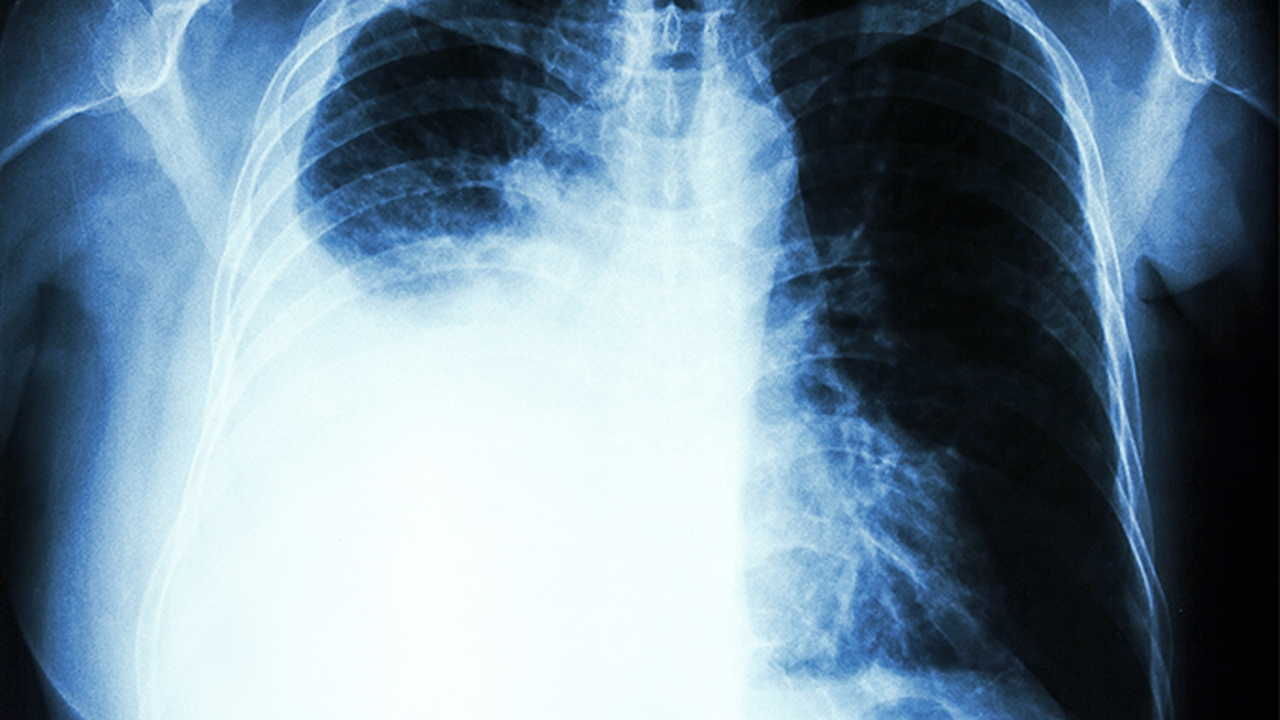

重症肺炎可能出现呼吸急促、口唇发绀等缺氧表现,老年患者或慢性肺疾病患者更易发生。轻度支气管炎一般无呼吸困难,但慢性支气管炎急性发作时可出现。血氧饱和度低于93%需吸氧治疗,严重呼吸衰竭可能需要无创通气。婴幼儿出现鼻翼扇动、三凹征提示病情危重。